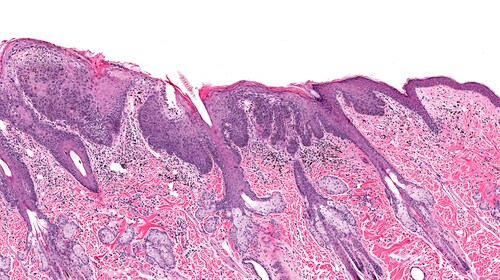

Tower et al. examined the frozen tissues with standard histological assessment to delineate the areas of cancer cells for further investigation. Once defined, they excised the tissue to extract proteins for sodium dodecyl polyacrylamide gel electrophoresis (SDS-PAGE), then used western immunoblotting to visualize phosphorylated biomarker levels.